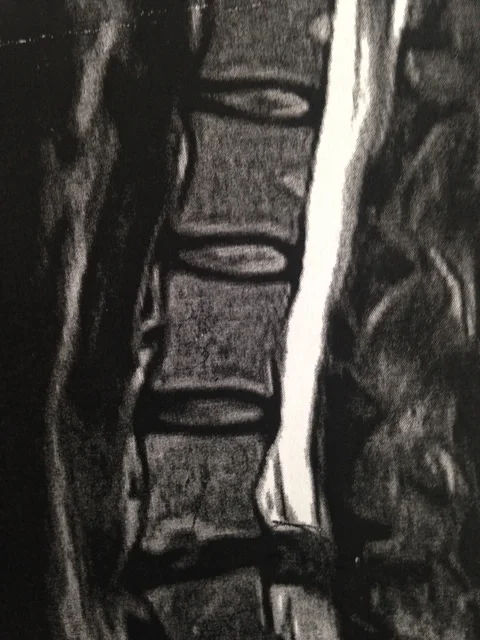

BEFORE

MRI scans showing before and after spinal decompression treatment